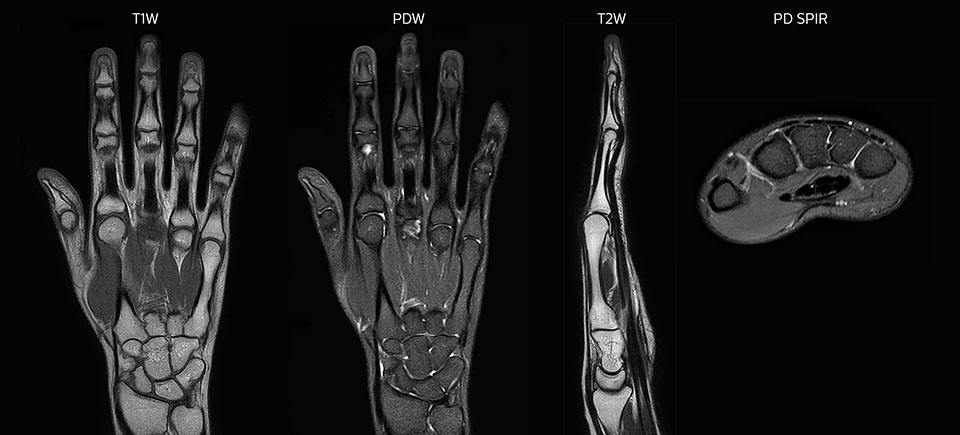

Prodiva imaging of the hand covers the fingertips and includes the full wrist as well. The dS MSK M coil is easy to use.

The Prodiva shoulder coil is very flexible and has large coverage, which makes good positioning easier, and that contributes to the superb image quality and high SNR that we get in our shoulder exams.

Scan time 2:55 min, FOV 160 mm, acq voxels 0.55 x 0.83 x 3.0 mm.

Scan time 4:19 min, FOV 160 mm, acq voxels 0.55 x 0.80 x 3.0 mm.

Scan time 2:50 min, FOV 160 mm, acq voxels 0.70 x 0.99 x 3.0 mm.